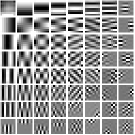

First, we study transform training based on Mayo Clinic data. As shown in Fig. 6, seven slices obtained at regular dose from three patients are used for transform learning. The number of pixels . Similar to the phantom experiments, overlapping patches are extracted with a patch stride. The number of overall training patches is about . We set for ST, , , for MARS2, , , , , for MARS3, , , , , , , , , for MARS5, , , , , , , , , , , , , for MARS7. The iteration number in Algorithm 1. Fig. 7 illustrates the learned transforms obtained with Mayo Clinic data. Different from the XCAT phantom case, these transforms up to MARS5 display more complex features and structures. The rich features of the MARS models better sparsify the training images over layers compared to the single-layer model (ST).